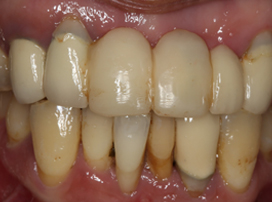

FAILING TOOTH

Card image Actual Practice Photographs ©Dr.Pavan Bopanna